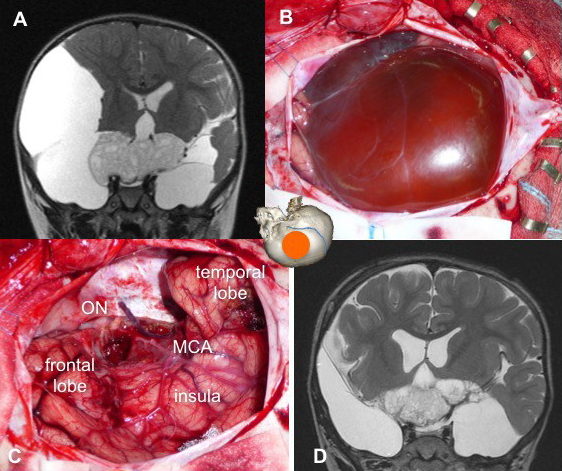

- par voie ptérionale

il permet une décompression par vidange d’un kyste, des prélèvements anatomo-pathologiques, et une résection en règle générale partielle voire très partielle. selon le développement antérieur ou supérieur de la tumeur, on aborde :

- par voie ptérionale (cf. ci-dessous)